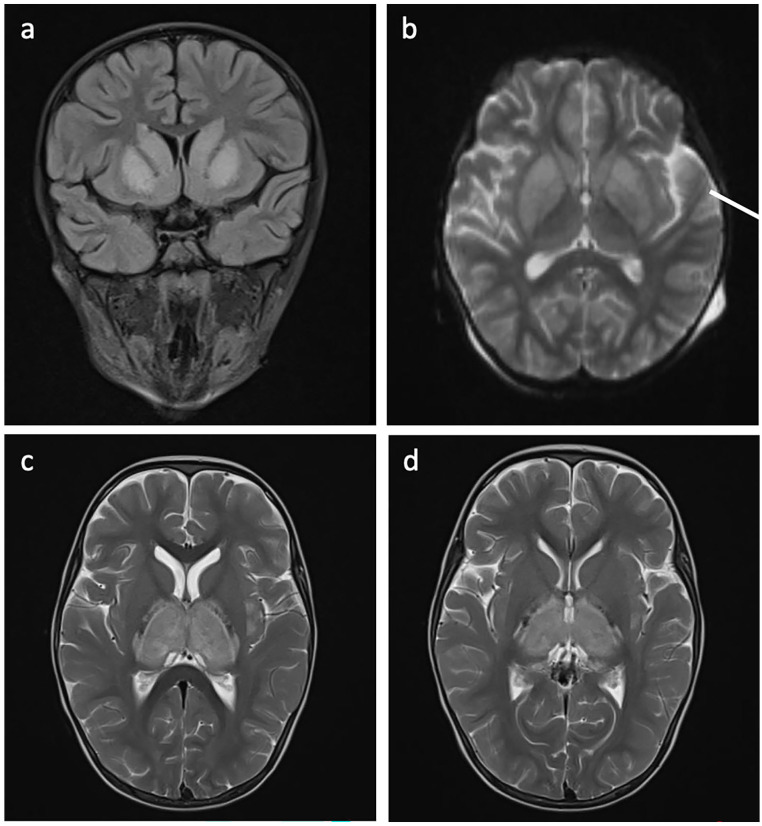

Objectives. This study aims to report clinical features and treatment outcomes of 16 cases diagnosed with post-influenza encephalopathy/encephalitis. Methods. We recorded clinical characteristics of 16 pediatric patients diagnosed with post-influenza encephalopathy/encephalitis at the Vietnam National Children's Hospital from January 2019 to January 2021. Results. There were 87.5% infected with influenza A, with influenza A/H1pdm09 and influenza A/H3 accounting for 88.9% and 11.1% respectively, and 12.5% of participants infected with influenza B. The time from onset to the appearance of neurological symptoms was 3 days, of which perceptual changes (93.8%), hypertonia (75%), and seizures (43.8%) were prevalent neurological symptoms. The majority of cases had normal cerebrospinal fluid. Cranial CT/MRI imaging revealed abnormalities in 87.5% of patients. 56.3% of patients had sequelae, including epilepsy and cerebral palsy; 25% recovered, and 18.8% died after treatment. Conclusions. Influenza-associated encephalitis/encephalopathy is a complication occurring early in children, with high mortality and sequelae rates.